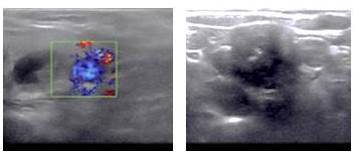

Acude a nuestro centro donde es evaluada al examen físico se encuentra paciente en regulares condiciones generales, afebril, hidratada, eupneica, deambulando sin ayuda. En el área de cabeza y cuello se evidencia glándula tiroides de tamaño normal, se palpa en lóbulo izquierdo nódulo de 1 cm, no doloroso. Se palpa lesión pétrea, calcificada en nivel IV derecho. Se le realiza nasofibrolaringoscopia evidenciando parálisis de cuerda vocal izquierda. Se evalúa el ultrasonido tiroideo que reporta imagen nodular sólida con gruesas calcificaciones centrales compatibles con adenopatía calcificada que mide no menos de 25 mm x 30 mm, en fosa supraclavicular derecha. En el polo inferior de la glándula tiroides se aprecia pequeña imagen nodular ecomixta, compatible con adenoma con degeneración quística que mide 9 mm. El lóbulo izquierdo se aprecia nódulo sólido hipoecoico que mide 15 mm x 20 mm compatible con adenoma sin degeneración quística (Figura 2).